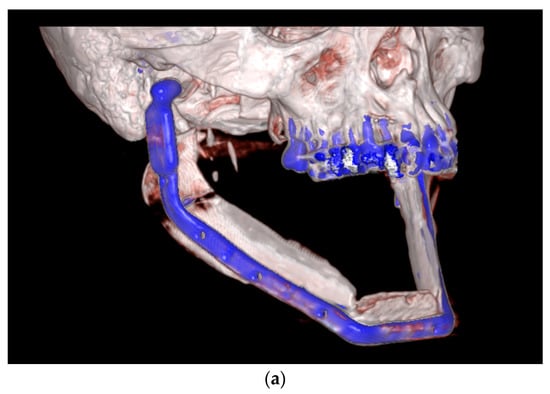

| July 2014: | Diagnosis of MRONJ in the right molar region of the mandible. Following mandibular box resection and protective plate osteosynthesis with a patient-specific plate. |

| August 2018: | Partial mandibular resection with continuity defect and alloplastic reconstruction using a patient-specific plate, excision of a submental fistula |

| September 2022: | Partial mandibular resection from the left mandibular angle to the right mandible, including the right temporomandibular joint, CAD/CAM-guided reconstruction with a bilateral free scapula flap with skin island, and patient-specific plate. In the course: